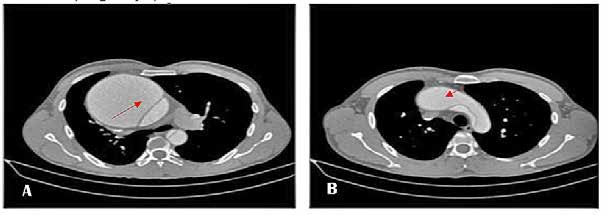

Tomografía computarizada (TC) de tórax. Realizado cuatro horas posterior al ingreso del paciente (Imagen 1 y 2).

IMAGEN 1 . TC. Aneurisma voluminoso de la raíz aórtica que compromete la aorta ascendente que mide 14 x 13 cm, (Imagen A) Flap de disección que separa la luz verdadera de la falsa, dicho flap compromete la raíz aórtica, la aorta ascendente y se extiende hasta el extremo proximal de la aorta descendente (Imagen A y B).